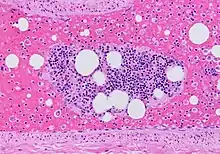

- Kumar V, Abbas AK, Fausto N, Mitchell RN (2010). Basic Pathology. New Delhi: Elsevier. p. 98. ISBN 978-81-312-1036-9.